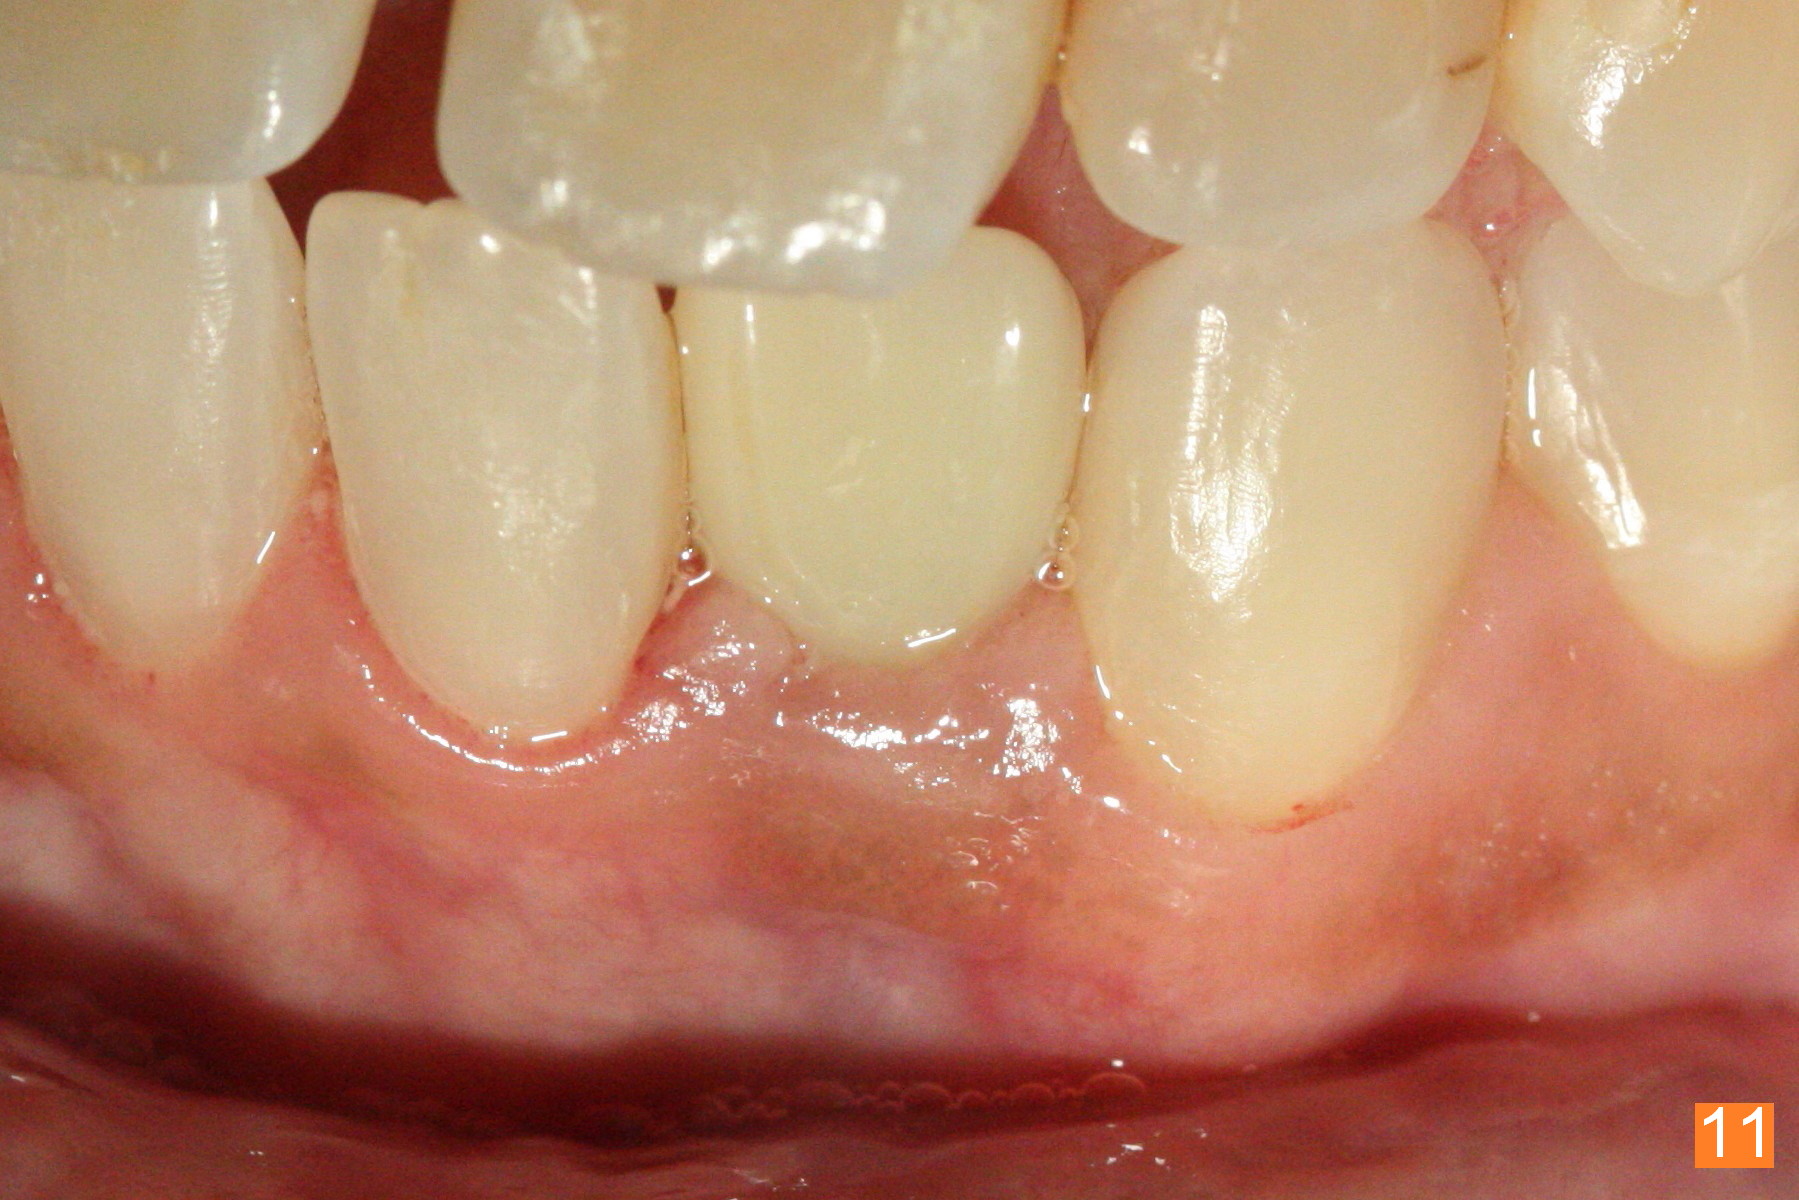

Fig.10: A2 shade guide.  The patient requests A1 for the incisal edge and body and A2.5 for the cervical region.  Fig.11 is taken 22 months post 2nd cementation (4 years postop).  The implant crown remains normal 1 year 10 months post 2nd cementation (4 years 10 months postop, Fig.12,13).